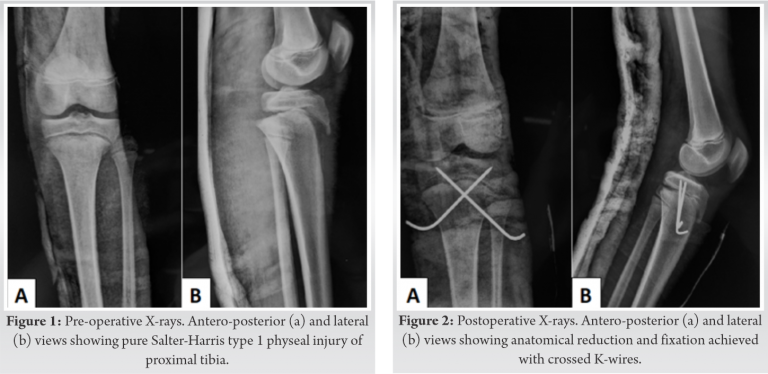

Radiographs revealed SH I proximal tibial physeal injury with posteriorly displaced tibial metaphysis (Fig. 1). Doppler sonography revealed a monophasic flow in the anterior tibial, posterior tibial, and dorsalis pedis arteries. The flow was normal above the level of the injury.

He was shifted to the operating room within 45 min of presentation. Under general anesthesia, in supine position, the fracture was reduced in a closed manner with traction and extension followed by flexion at the fracture site. Care was taken not to hyperextend or hyperflex the limb at any time during the maneuver. The reduction was held with two thick smooth K-wires in a crossed configuration (Fig. 2). The patient’s peripheral pulses had returned by the time the fixation was completed and hence the circulation was restored. Pin prick bleeding and capillary refill time returned back to normal. This was confirmed with a portable Doppler which showed biphasic flow in the peripheral arteries. Patient’s knee was immobilized in an above knee plaster cast. The post-operative period was uneventful except that the patient developed some blisters in the proximal leg on the 3rd postoperative day; however, there were no signs of any neurovascular compromise. The blisters were punctured, painted with Povidone-iodine and dressed in a dry manner. The skin healed well in a few days and the patient was discharged. The cast was removed at 3 weeks following which knee range of motion was started and the K-wires were removed at 6 weeks. Weight bearing was allowed at 3 months and gradually progressed as tolerable. Radiological healing was seen at 4 months (Fig. 3). At the last follow-up of 1 year, the patient had a good knee range of motion (ROM), no limb length discrepancy or deformity and was able to squat and sit cross legged without any difficulty.